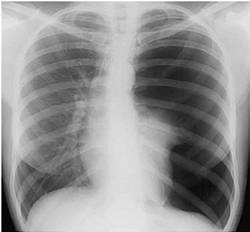

Науқас 25 жаста, жіті ауырып қалды. Безгектік және құрѓақ жөтел пайда болды, оң жақ бүйірінен ауырсыну қосылды. Оң жақ өкпенің астын перкуссиялағанда өкпе дыбысы женіл әлсіреді, аускультацияда дем алуы бәсең. Кеуде қуысы мөшелеріне 2-і стандартты проекцияда рентгенография тағайындалды.

Нақты клиникорентгенологиялық сурет қай ауруға сәйкес келеді:

{Дұрыс жауабы} = C